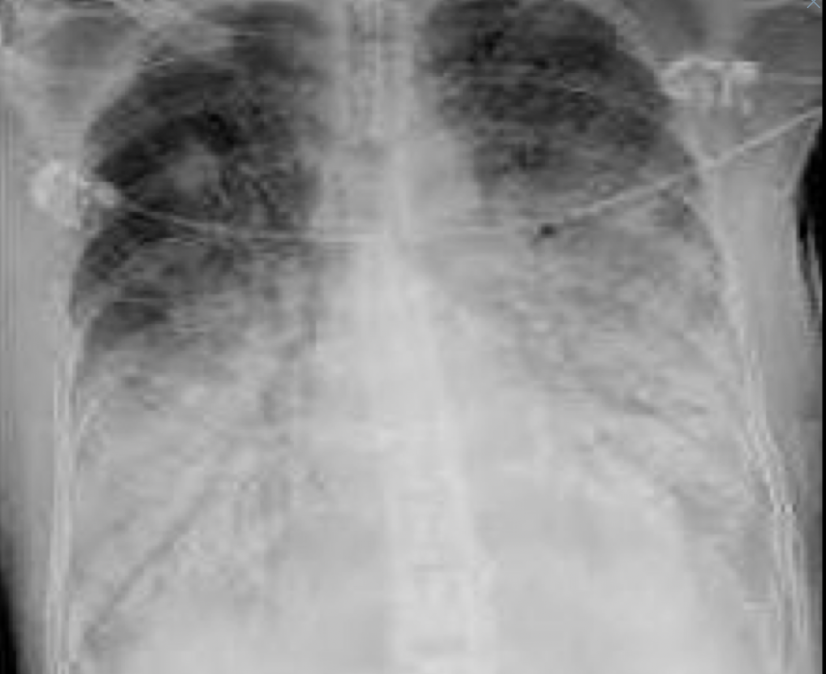

Que patrón pulmonar es

A

Intersticial/reticular

Q

que patrón pulmonar es?